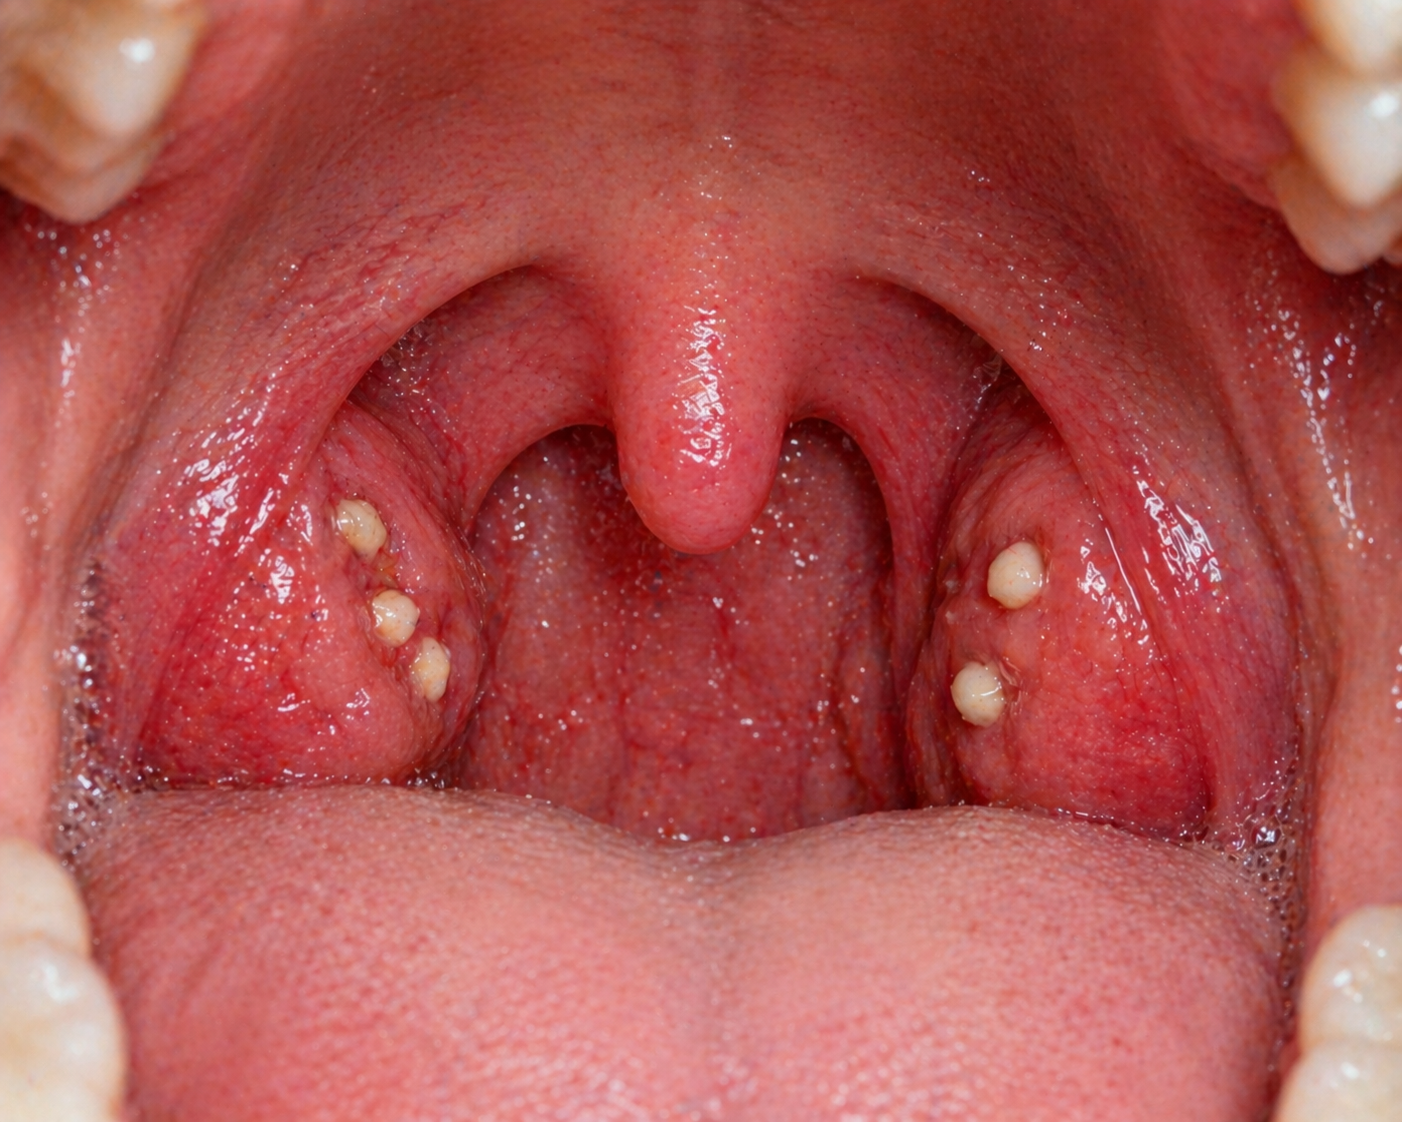

어떤 날은 기침하다가 작은 하얀 알갱이가 나와서 놀라기도 한다. 거울을 보면 편도 쪽에 하얀 점처럼 보이는데, 처음 보면 꽤 낯설게 느껴진다. 심한 경우에는 목이 따끔거리거나 염증이 생긴 것처럼 불편할 수도 있다. 이러한 증상은 심하지 않더라도 계속 신경 쓰이게 만든다. 계속 이물감이 느껴지고 불편하다면 편도 결석을 의심해봐야 한다.